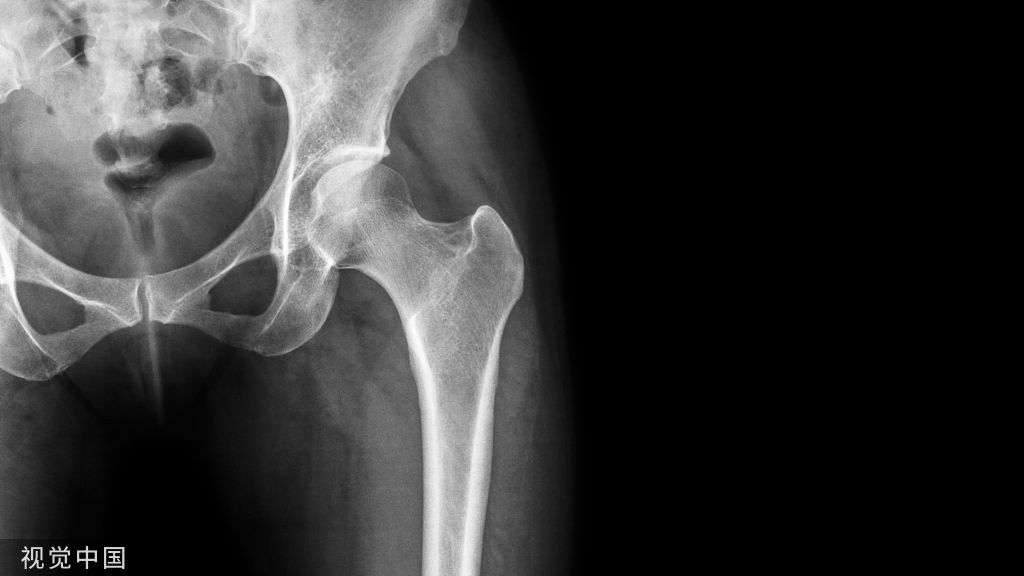

原发性骨质疏松症预防及治疗用药方案如下图,药品具体解读在后面,请仔细阅读。

预防

治疗